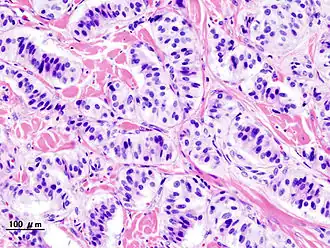

Description de l'image Pancreatic insulinoma (2).JPG.

Le nésidioblastome, est une tumeur pancréatique langerhansienne. Elle fait partie des tumeurs neuroendocrines.

Le nésidioblastome peut être bénin ou malin. Dans ce dernier cas on parlera d'épithéliome ou de carcinome langerhansien. Le nésidioblastome doit son deuxième nom au fait qu'il entraîne une production excessive d'insuline, qui part dans le sang et donc entraîne une hypoglycémie. La tumeur est donc dite endocrine car elle sécrète une hormone (l'insuline) dans le sang.